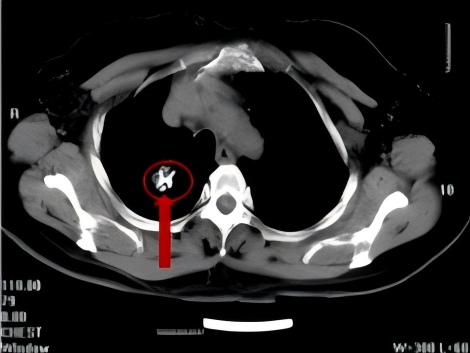

68岁患者,因长期咳嗽、气喘、气急等症状前来我院呼吸与危重症医学科就诊,在进行CT检查后,发现患者右肺存在肿瘤,进一步完善相关检查后,诊断为右肺鳞癌IIIB期,因考虑到患者肿瘤较大,需切除大部分肺组织,对肺功能影响非常大,在充分尊重患者意愿下,科室为患者制定了多种治疗方案,最终患者选择了CT引导下经皮肺穿刺碘125粒子植入治疗。综合治疗5月后,患者病灶明显缩小,2年后复查,患者病灶稳定。

碘125粒子植入术后

综合治疗5月后

综合治疗2年后